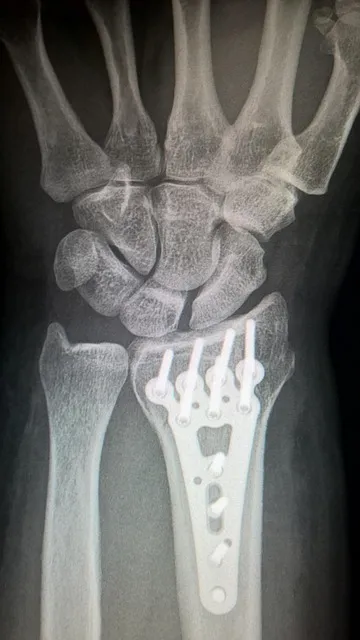

手术治疗是处理移位性、开放性或严重不稳定骨折的主要方案。常用的手术技术包括钢板内固定、螺钉复位、髓内钉固定等方式,用以恢复关节力线及骨折稳定。术中需保护组织完整及血供,术后辅助康复疗程促进功能恢复。